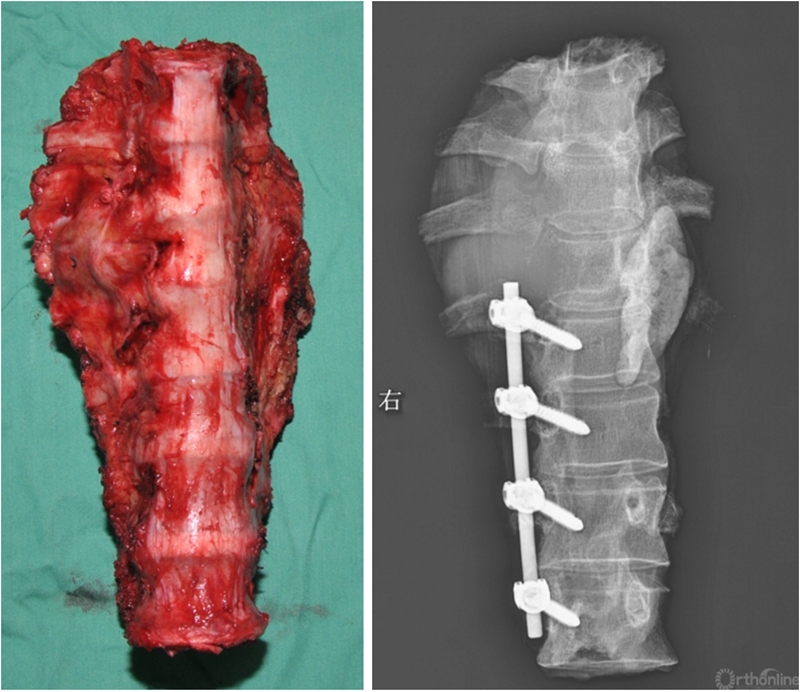

七椎体整块切除

3D打印人工椎体精准植入

世界首例

2021年底空军军医大学唐都医院收治了一位特殊的病人,恶性纤维肉瘤侵蚀了患者的七节椎体,在背部形成破溃,并且造成了截瘫,整块切除的难度和危险性很大,切除后的重建也极具挑战性。术前团队与全院多个科室反复推敲模拟手术过程,制定手术方案。为了重建脊柱缺损,团队决定采用3D打印技术为患者量身定制钛合金人工椎体,确保脊柱稳定性。术中骨科、整形外科、胸外科,烧伤科、麻醉科等专家通力协作,手术全程18个小时,术后患者恢复良好。经过科技查新,这是世界首例脊柱七椎体肿瘤整块切除重建案例。回顾全程,团队完成了一场考验经验丰富度、协作默契度、工作认真度的实践大考,也着实打赢了一场酣畅淋漓的硬仗。